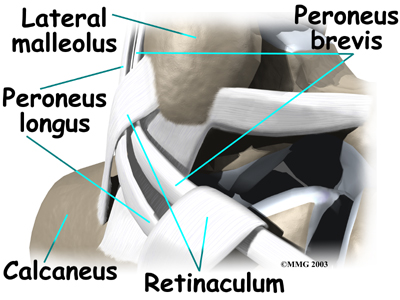

The peroneals are two muscles and their tendons that lie along the outside of the lower leg bone (the fibula) and cross behind the lateral malleolus (the outer ankle bone). The term medial refers to a point closer to the center of the body. So the ankle bump on the inside edge of the ankle (closest to your other ankle) is the medial malleolus. The term lateral refers to structures furthest from the center. Major muscles that support the lateral part of the ankle are the peroneus longus and the peroneus brevis.

The tendons of these two muscles pass together in a groove behind the lateral malleolus. (Tendons attach muscles to bones.) The tendons are kept within the groove by a sheath that forms a tunnel around the tendons. The surface of the tunnel is reinforced by a band of tissue called a retinaculum. Contracting the peroneal muscles makes the tendons glide in the groove like a pulley. The pulley action causes the foot to point (plantarflexion) and (eversion).

The connects to a bump on the base of the fifth metatarsal. This spot can be felt midway down the outer edge of the foot.

The lies behind and below the peroneus brevis tendon. It wraps down and under the foot by way of the cuboid bone, the outer tarsal bone just in front of the heelbone (the calcaneus). The peroneus longus tendon angles forward under the sole of the foot and connects to the bottom of the main bone of the big toe. This tendon stabilizes the arch of the foot when walking.